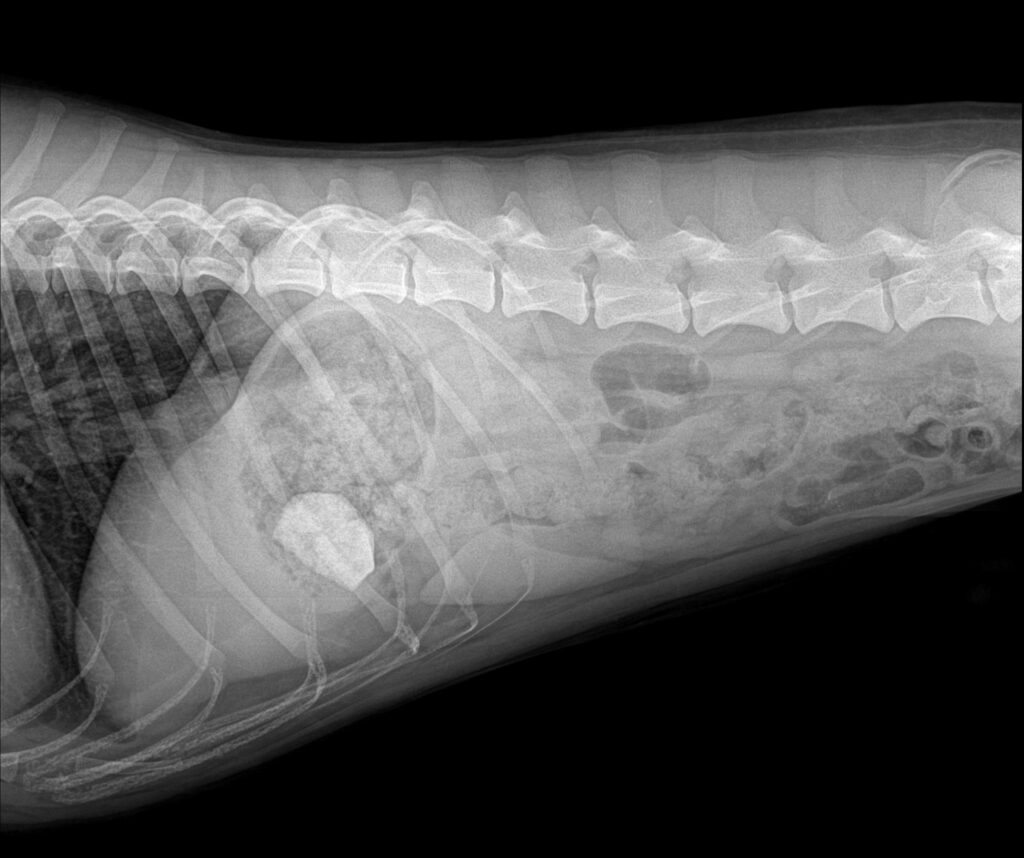

수술 후 방사선 사진 / 출처: 미래동물의료센터